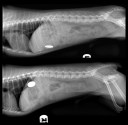

Archives de catégorie – Ils ont mangé quoi ?

• Ils ont mangé quoi ? (18)